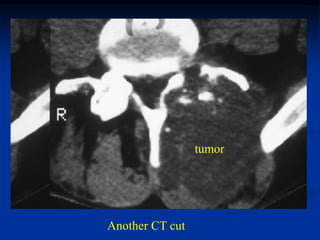

Case #1103

34 year male with

chordoma L-5

tumor

CT scan at L-5 shows chondroid like tumor arising from

the postero-lateral elements of L-5

Another CT cut

Another